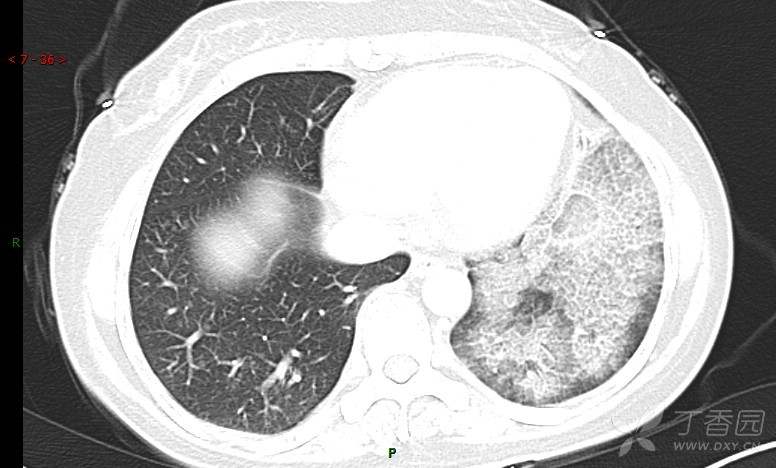

腺泡结节影,蜂窝征,这些都在提示……(病例3连发,附其他2例链接,病理已公布)

咳嗽1年余,加重7天。

患者于1年余前始受凉后出现咳嗽,多为干咳,未在意,未到医院就诊。近3月患者出现咳痰,多为黄色粘痰,量大,伴乏力,偶有头晕、心慌,无发热、胸痛、憋喘,无低热、盗汗、咯血、胸痛,无头痛,无恶心、呕吐、腹痛、腹泻,无尿频、尿急、尿痛,在当地诊所给予抗感染等对症支持治疗(具体药物及剂量不详),症状仍时有反复。患者于1月余前到外院就诊,行胸部CT提示双肺炎症,左肺重,考虑为“间质性肺炎”,给予“左氧氟沙星、利巴韦林、头孢哌酮舒巴坦钠注射液”治疗,复查胸部CT示病灶吸收不理想,后出院继续于诊所对症治疗(具体药物及剂量不详),效果欠佳。7天前患者无明显诱因出现上述症状加重,为求进一步诊治,特来我院就诊,我院门诊以“肺炎(重症)?”收入留观室,留观室给予“盐酸莫西沙星氯化钠”等对症治疗后,今日转入我科。患者自发病以来,神志清,精神差,饮食正常,睡眠增多,大小便正常,体重近3月减轻5公斤余。